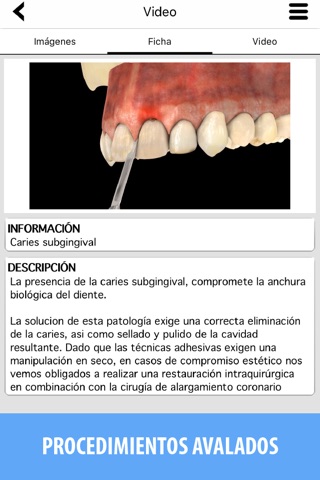

Todos los procedimientos incluidos son responsablemente seleccionados y avalados por los mejores profesionales del área en España y Europa.

- Información para los pacientes.